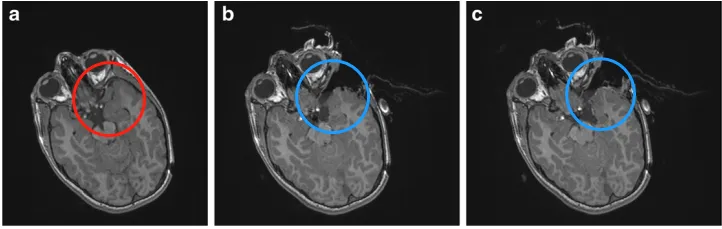

病例二:左颞神经节神经胶质瘤

一名8岁男孩,曾有全身性癫痫反复发作、进行性加重及说话能力受损病史。大脑磁共振显示其存在“左颞叶病变”(下图a)。随后,在术中神经导航和术中磁共振成像(iMRI)系统的辅助下,经左颅骨开颅手术治疗。术中,病变边缘与正常组织难以区分。在评估认为肿瘤可全切后,进行了术中MRI检查,结果显示在颞后肌膜区域仍有肿瘤残留(下图b)。随后,使用更新后的导航图像继续手术,如第二次术中MRI对照所示,最终实现了肿瘤全切(下图c)。术后患者状态平稳,组织学结果显示为神经节神经胶质瘤(WHO 1级)。为期1年的随访中,无肿瘤复发,且癫痫未再发作。

图:a为左颞神经节神经胶质瘤(WHO I级)的术前MRI。b为术中MRI控制显示在颞后肌膜区域残留肿瘤。c继续手术,术中第二次MRI显示病变已全切。